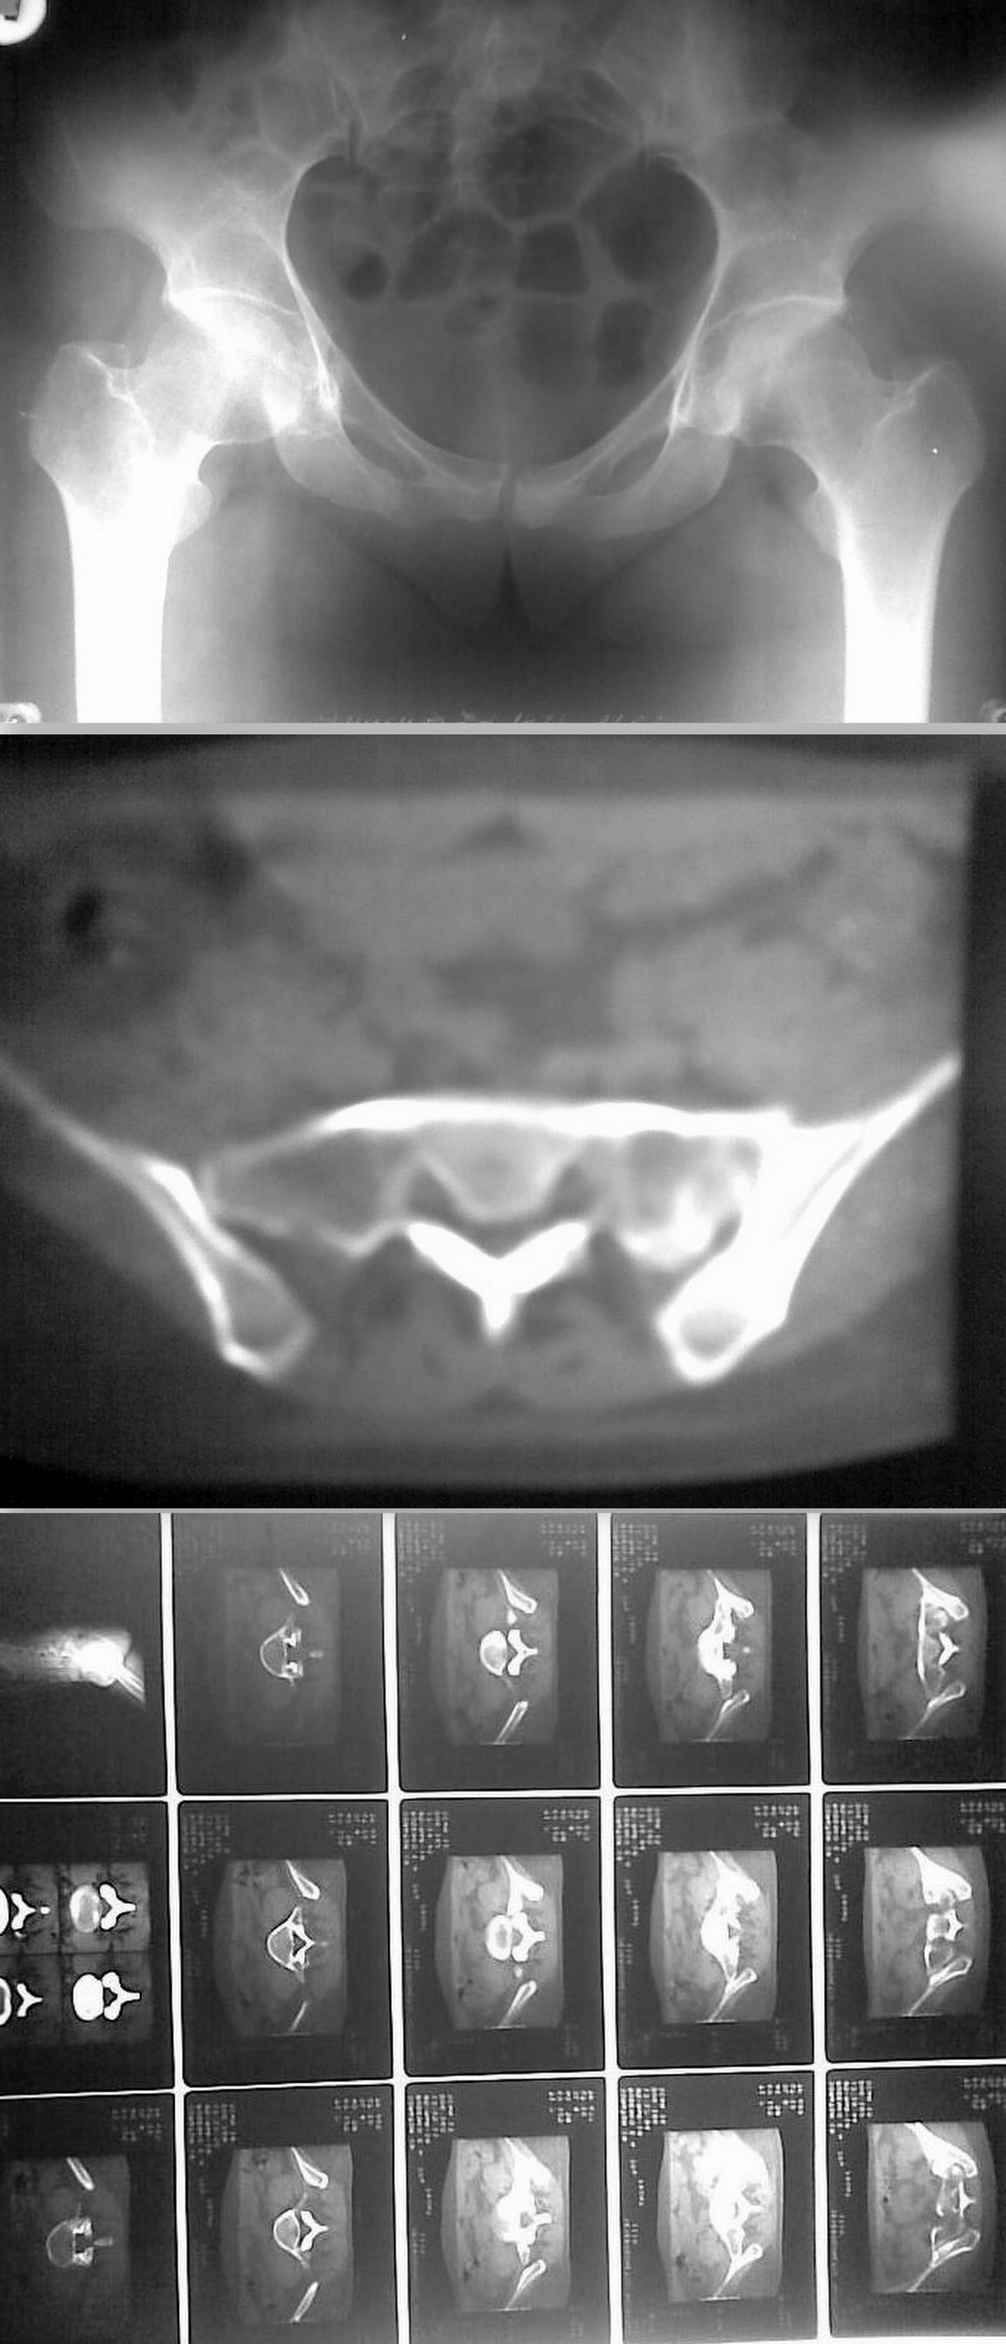

Добрый вечер, уважаемые коллеги. Представляю на обсуждение случай "несвежего" перелома крестца.Больная 32 лет поступила в отделение 02.03.10. Травма 26.12.09 ДТП в качестве пассажира (сидела сзади, машина перевернулась)Находилась на амбулаторном(?)лечении с диагнозом "перелом седалищной кости справа" . через 2 месяца после травмы больная вертикализирована, но отмечались интенсивные боли в поясничном отделе с иррадиацией по задней поверхности бедра. Больная направлена в стационар. Выполнено КТ.Картина в приложении.